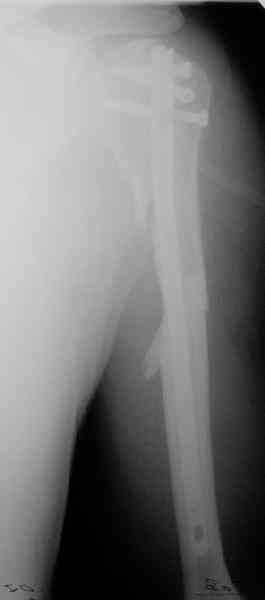

Попытка закрыто изменить положение не удалась. Передним доступом сделали открытую репозицию, гленоид без особенностей. Временно фиксировали спицами и остроконечным костедержателем. Фиксировали гвоздем T2 PHN (Stryker). Для профилактики вывихов после введения проксимальных винтов ротировали дистальный отдел кнаружи на 30

градусов как аналог остеотомии по Weber. Снимки в приложении. Комментарии и критика привествуются.

Attempt of closed reduction failed. Open reduction via anterior approach. The head was temporarily fixed by wires and sharp clamps. Fixation by a nail - T2 PHN (Stryker). The distal fragment has been rotated 30 degrees externally after proximal locking for dislocation prevention as "virtual" Weber osteotomy. Images attached.

Comments/critics are welcome.

To my mind it was most suitable for this injury because of long shaft extension.

> Is there only a single screw in the head?

All 3 screws are in the head. The feature of the nail is that it has four holes oriented not 45 degrees to frontal or sagittal planr, but anatomically to the head and both tubercles. The holes in the nail are threaded so angular stability is perfect, and contain a nylon bushing

preventing any screw rotation/back out.

Frankly speaking I am not sure about over-rotation. I requested the

patient to check these days if the shoulder feels comfortable. If not we are able to remove the distal screw, change rotation and re-lock the

nail.